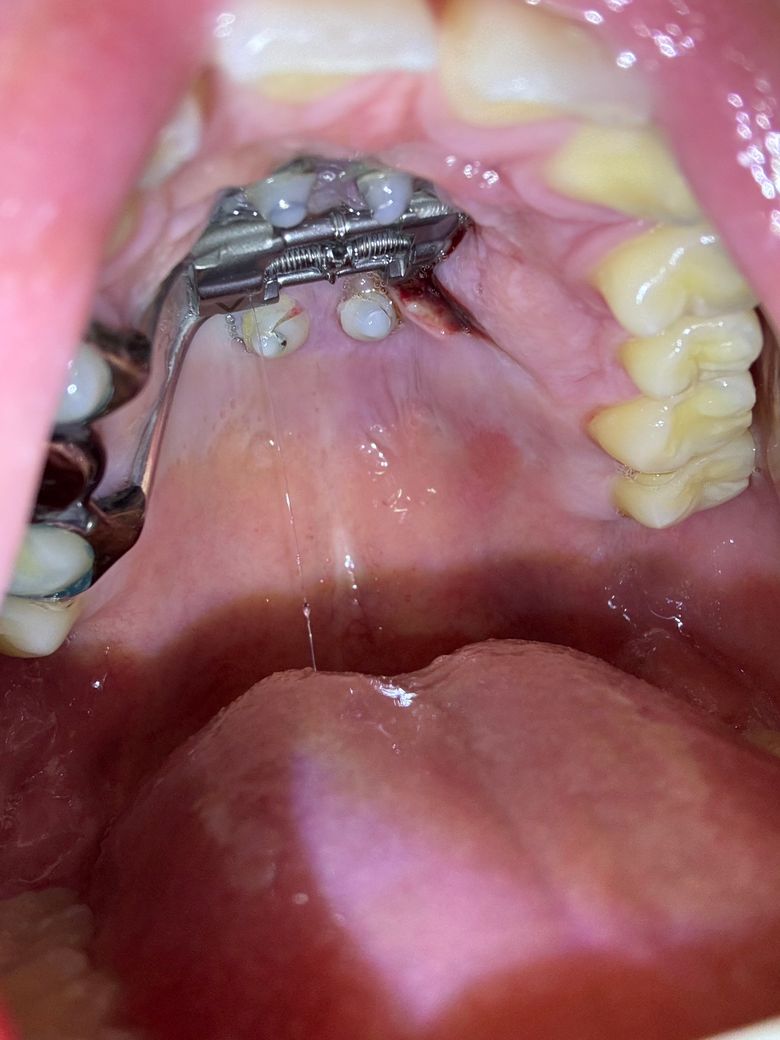

잇몸을 잘라냈는데 괜찮은 건가요??

악궁 장치 다리가 잇몸을 압박해서 염증이 났습니다.

그래서 오늘 악궁 장차 다리랑 염증 부위를 좀 잘라냈는데 사진으로 보니까 상처가 좀 많이 벌어진 것 같아서요. 괜찮을까요? 피는 멎었습니다

• 2번 째 사진

상처부위가 많이 벌어져있어 회복이 더딜 수도 있어보입니다. 해당 치과에 문의해보시는 게 좋겠습니다.

잇몸에 상처는 시간이 지나면 아물게 되며, 해당부위 염증이 덧나는 것을 막기 위해 소독용 헥사메딘 가글액으로 가글하여 관리를 하여주길 권합니다.

또한 자극감을 줄수 있는 맵고 짠음식 너무 뜨거운 음식은 피하길 권합니다.